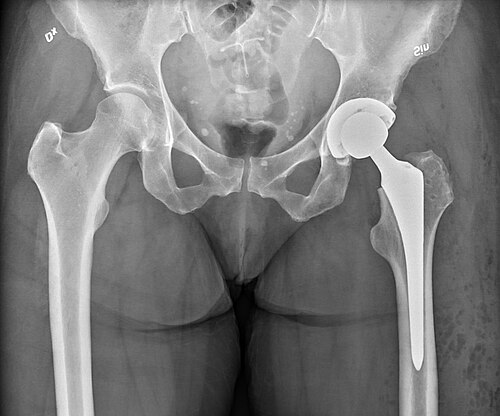

total hip arthroplasty is a surgical procedure that replaces the hip joint with prosthetic components to relieve pain and restore function. It is performed worldwide by orthopedic surgeons in hospitals associated with institutions such as Mayo Clinic, Cleveland Clinic, Johns Hopkins Hospital, and university centers like Harvard Medical School and University of Oxford. Indications, techniques, implants, outcomes, and rehabilitation pathways are influenced by guidelines and research from organizations including the World Health Organization, National Institutes of Health, American Academy of Orthopaedic Surgeons, and specialty journals affiliated with The Lancet and New England Journal of Medicine.

Implant types and materials

Implants vary by femoral stem design, femoral head size, and acetabular component, produced by manufacturers with partnerships involving Johnson & Johnson, Zimmer Biomet, and Stryker Corporation; devices are evaluated in registries like the National Joint Registry (UK) and studies from institutions such as Ludwig Maximilian University of Munich. Materials include metal-on-polyethylene, ceramic-on-ceramic, and metal-on-metal bearings; ceramic components trace metallurgy and ceramics science collaborations with laboratories at Imperial College London and ETH Zurich. Cemented prostheses utilize bone cement developed with companies that have interacted with Baxter International, while porous coatings for biologic fixation were advanced in research at Duke University School of Medicine and University of Toronto. Modular designs and dual-mobility constructs were influenced by work at centers like Institut Mutualiste Montsouris and Aarhus University Hospital.